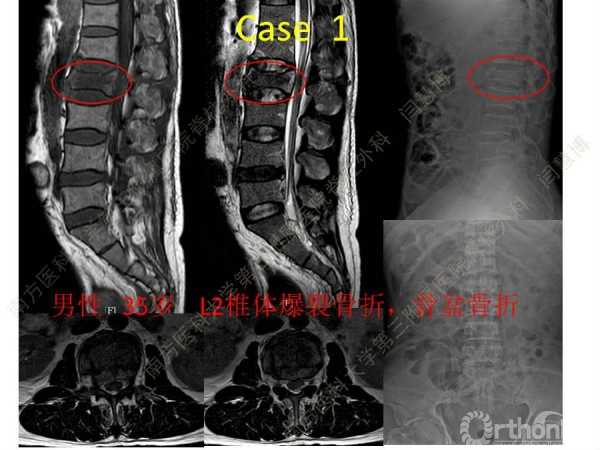

胸腰椎骨折是指由于外力造成胸腰椎骨质连续性的破坏,在如车祸、高处坠落等意外事故中,是最常见的脊柱损伤。老年患者由于本身存在骨质疏松,甚至有可能因为一些如滑倒、跌倒等低暴力因素导致胸腰椎骨折。胸腰椎骨折患者常合并神经功能损伤,且由于致伤因素基本为高能损伤,常合并其他脏器损伤,这为治疗带来了极大的困难和挑战。针对胸腰椎骨折,南方医科大学第三附属医院闫慧博教授介绍了他们运用微创方法治疗的经验。